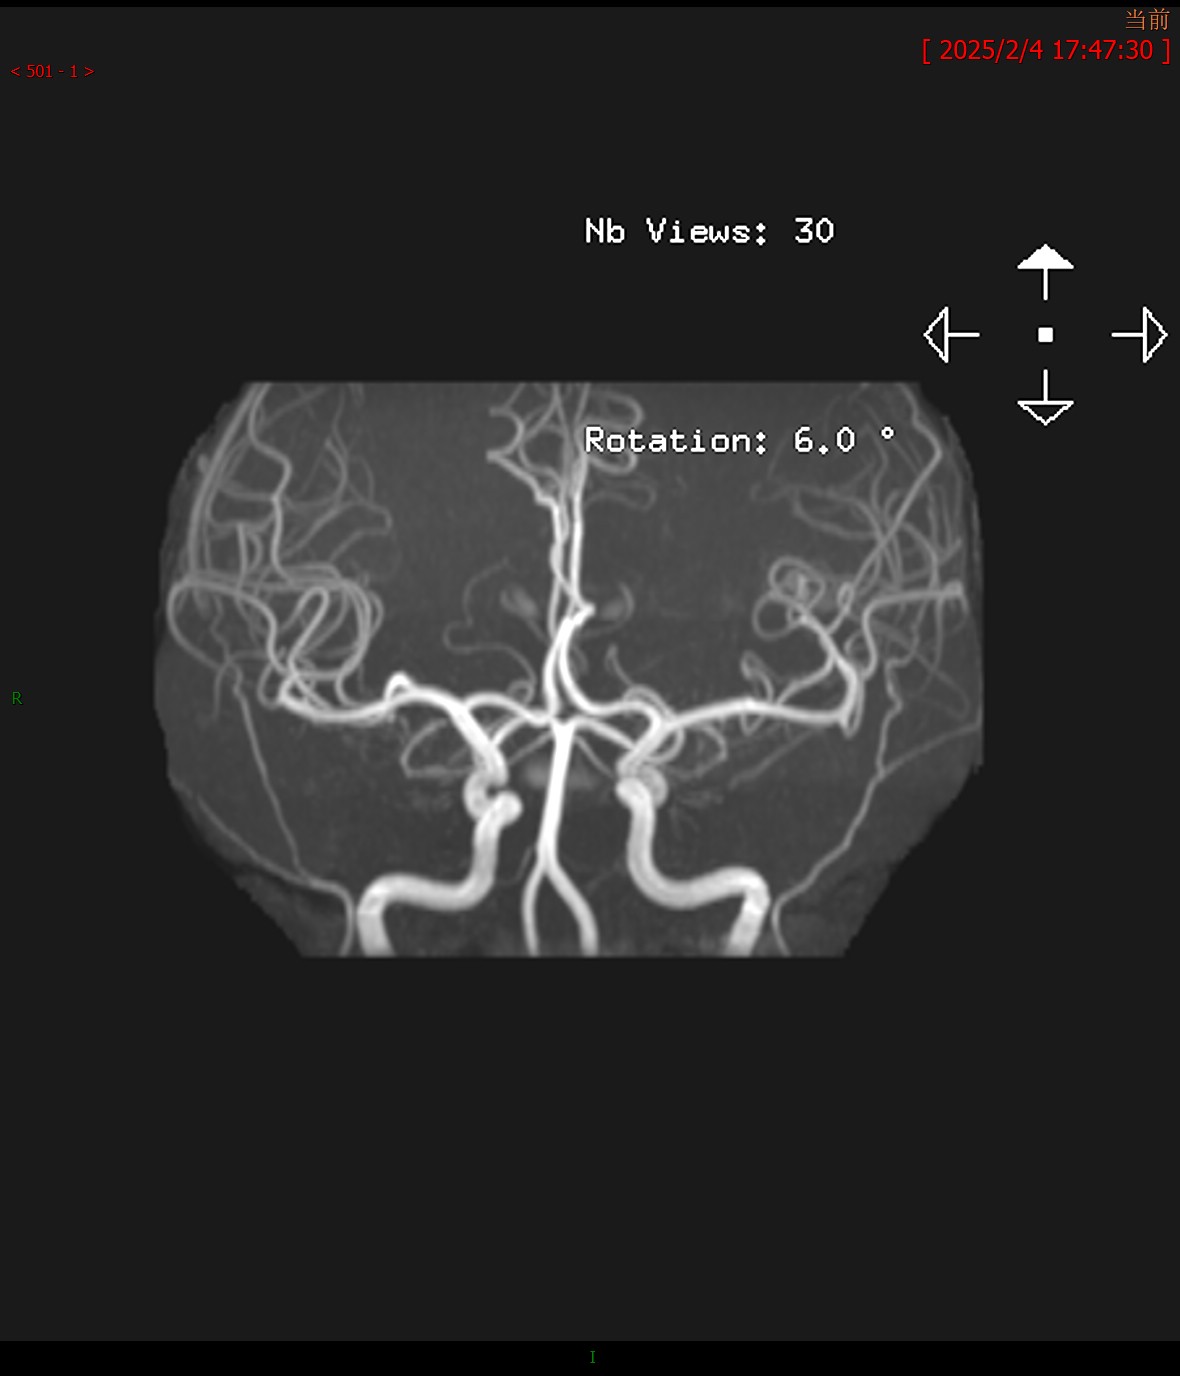

T2FLAIR横轴位 MRA

MRA颅脑MR平扫:双侧桥臂、右侧小脑半球、延髓、桥脑、中脑、双侧豆状核、壳核可见多发斑片状稍长T1、T2信号,边界不清,病灶于T2FLAIR呈高信号,大致呈对称性分布。脑室系统轻度扩大,脑沟、脑裂增宽,中脑、小脑体积缩小,中线结构未见移位。

颅脑MRA:双侧大脑前动脉、大脑中动脉、大脑后动脉主干及分支走行通畅,管壁光整,血管腔未见明显狭窄及异常扩张,未见畸形血管;双侧椎动脉、基底动脉及双侧颈内动脉颅内段通畅,管壁光整,管腔未见狭窄及异常扩张。

影像学诊断:1. 双侧桥臂、右侧小脑半球、脑干及基底核团多发异常信号伴脑萎缩改变,符合肝豆状核变性颅脑表现;2. 颅脑MRA未见明显异常。